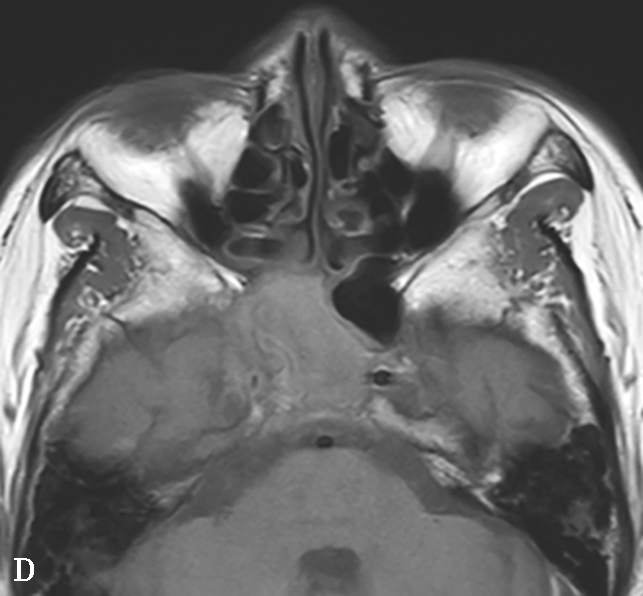

4.CT表现

①平扫表现:首先侵犯鼻部中线区,鼻中隔和双侧中下鼻甲及上颌窦内壁骨质破坏,伴有不规则索条影;双侧上颌窦腔缩小,黏膜增厚,窦壁骨质硬化、肥厚,可出现“双线”征;最终导致上颌窦内壁、筛窦间隔、纸样板、筛板、鼻甲和鼻中隔明显破坏而形成大空腔,类似术后改变。鼻窦周围软组织浸润,眼眶是该病窦外侵犯的首发部位,很少累及颅底、翼腭窝、窦后区和鼻咽部(图1-3-26A、B)。②增强扫描表现:鼻腔及鼻窦可见结节状及肿块样黏膜增厚强化。

5.MRI表现

①T 1 WI表现:呈低至中等信号的结节状肿块影。②T 2 WI表现:早期T 2 WI多为高信号,中晚期多为结节状肿块影(与高信号的水肿黏膜相比),提示为纤维组织,当病变呈急性加重并侵犯邻近的软组织时,表现为软组织水肿高信号。③增强扫描表现:病变区黏膜呈结节状或肿块状强化,周围受累组织呈明显不均匀强化(图1-3-26C~F),TIC(时间-信号强度曲线)整体呈平缓型,早期缓升,说明GPA与TIC单纯表现为平缓型的普通良性病变相比血管通透性更高或血管数量更为丰富,致使对比剂早期更易透过血管进入血液,产生更高的流速造成早期时相内曲线斜率略升高,这与该病的多血管炎症的发病机制密切相关。

图1-3-26 鼻腔鼻窦肉芽肿性多血管炎

A、B.横断面CT及冠状面CT骨窗,示鼻背部塌陷,鼻中隔、双侧筛窦及上颌窦黏膜增厚,窦壁骨质增生硬化,内缘骨皮质欠光整;双侧中、下鼻甲形态欠自然,双侧眼眶内下壁骨皮质部分缺损,邻近内下象限肌锥外间隙可见弥漫性软组织增厚影,右侧为著;双侧上颌窦口-鼻道复合体增宽,钩突缺如;C.横断面T 1 WI,示双侧上颌窦腔可见略低信号,气-液平面可见,鼻背部塌陷,鼻中隔黏膜增厚,鼻咽顶后壁软组织增厚,呈等信号;D.横断面T 2 WI,示上颌窦腔病变呈高信号,余病变呈略低信号;E.横断面T 1 WI+FS+C,示窦腔、鼻中隔增厚,黏膜及其他受累结构呈中等强化,双侧翼腭窝及上颌窦后脂肪间隙受累,强化;F.冠状面T 1 WI+FS+C,示双侧眼眶内下象限肌锥外间隙病变呈中等强化,大脑纵裂及额部脑膜受累,呈弥漫性增厚强化